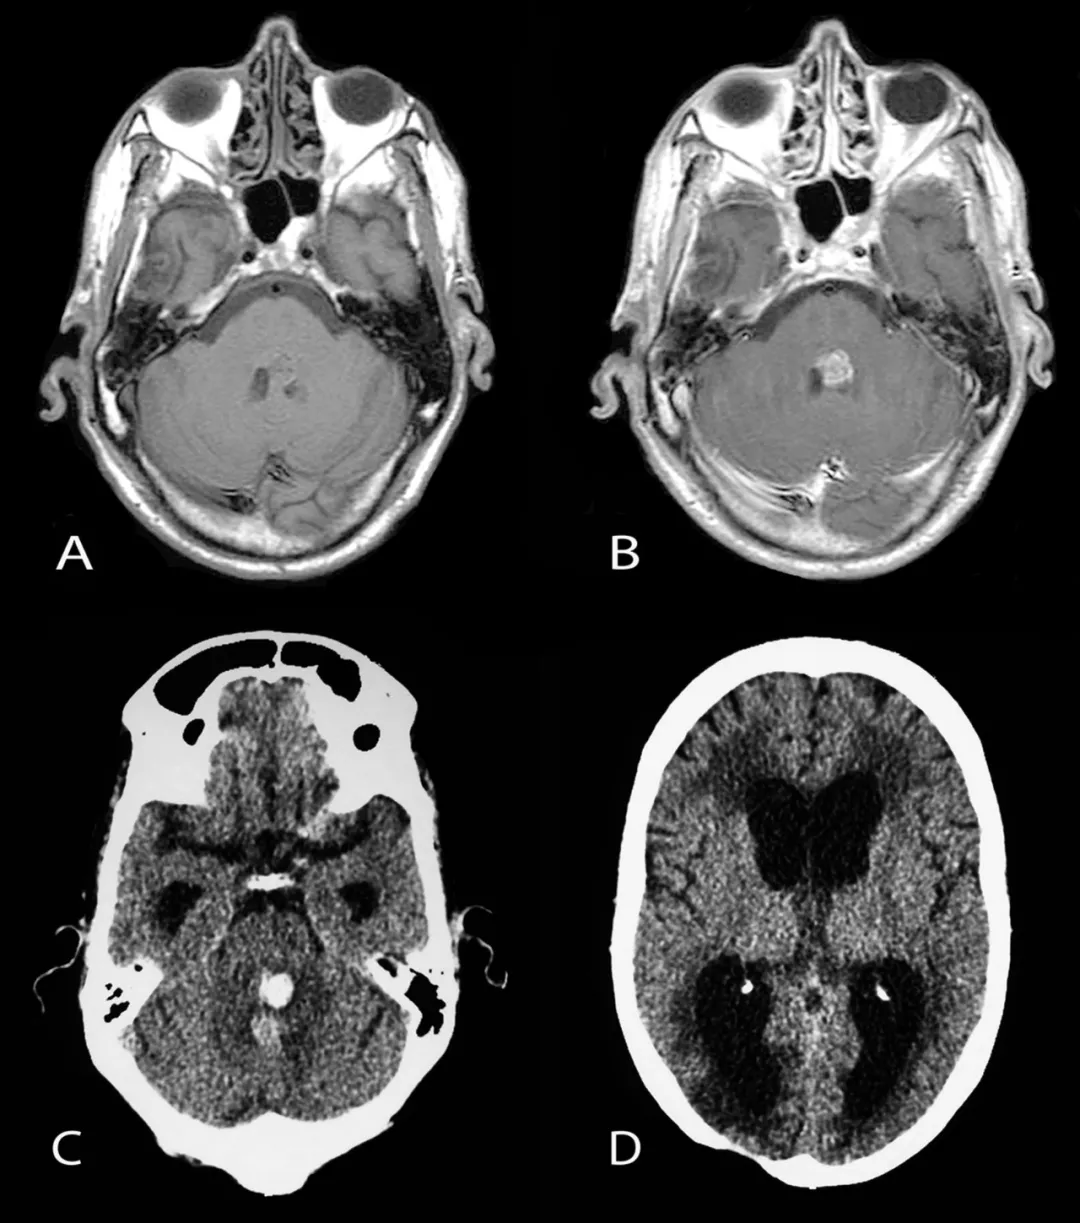

非脑干高级别胶质瘤的特征性磁共振成像表现包括T1加权像低信号、T2加权像皮质和白质高信号(表现为肿瘤浸润和血管源性水肿)以及不规则的强化。弥漫性内生性桥脑胶质瘤通常表现为一个大的、扩张性脑干肿块,中心位于脑桥,占据其三分之二。病变通常在T1加权像上呈低信号或等信号,边缘模糊不清,在T2加权图像上呈模糊的高信号,这反映了肿瘤的浸润性。但在液体衰减反转恢复序列图像上,弥漫性内生性桥脑胶质瘤经常显得相对均匀。这些肿瘤的对比增强可能是可变的,但无明确的预后意义。

弥漫性内生性桥脑胶质瘤

弥漫性内生性桥脑胶质瘤是常见于5岁至10岁儿童的高度恶性、进展迅速的侵袭性肿瘤。中位生存期约为9个月。临床表现通常是颅神经功能障碍、长束征和共济失调。此外,还可能存在继发于脑室梗阻的颅内压升高迹象。症状持续时间通常很短。1型神经纤维瘤病患者的病程可能相对缓慢。弥漫性内生性桥脑胶质瘤的诊断标准通常基于明确的磁共振成像表现,因此,活检常被视为不必要。

治疗弥漫性内生性桥脑胶质瘤的挑战在于其恶性的高级别组织学特征及其位于脑干中心区域这一特殊性。目前的重要治疗手段是放疗,手术仅限于活检,而活检主要用于磁共振成像表现不典型、不确定,或当研究方案有此要求时。立体定向活检已被证明是安全的。化疗在弥漫性内生性桥脑胶质瘤管理中的作用仍在评估中。